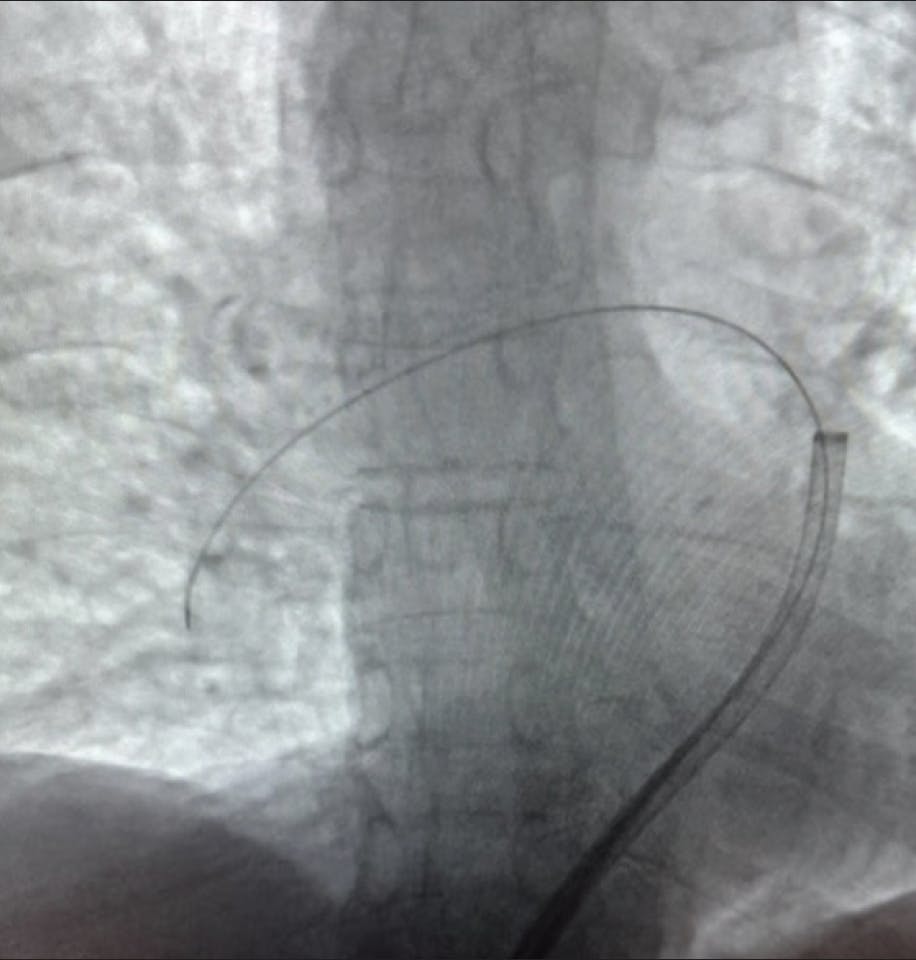

INTERVENTION

The right common femoral artery was cannulated, and angiography revealed a 100% occlusion of the proximal left circumflex (LCX) artery (Figure 1). The left main was engaged using a 6-F EBU 3.5 guide catheter, and a Runthrough wire (Terumo Interventional Systems) was placed in the LCX artery. A 2-mm semicompliant balloon was advanced and inflated at 12 atm, with the goal of restoring flow in the vessel (Figure 2). However, despite angioplasty, there was no improvement, and the vessel continued to have TIMI 0 flow (Figure 3).

Figure 1. 100% LCX artery occlusion.

Figure 2. Balloon angioplasty as initial device.

Figure 3. TIMI 0 flow after intervention.

The patient became increasingly hypotensive, requiring escalating doses of pressors and eventually mechanical support in the form of a percutaneous left ventricular assist device. During the procedure, the patient developed pulseless ventricular tachycardia requiring cardiopulmonary resuscitation and intubation, with eventual return to spontaneous circulation. He required a prolonged intensive care unit admission thereafter.